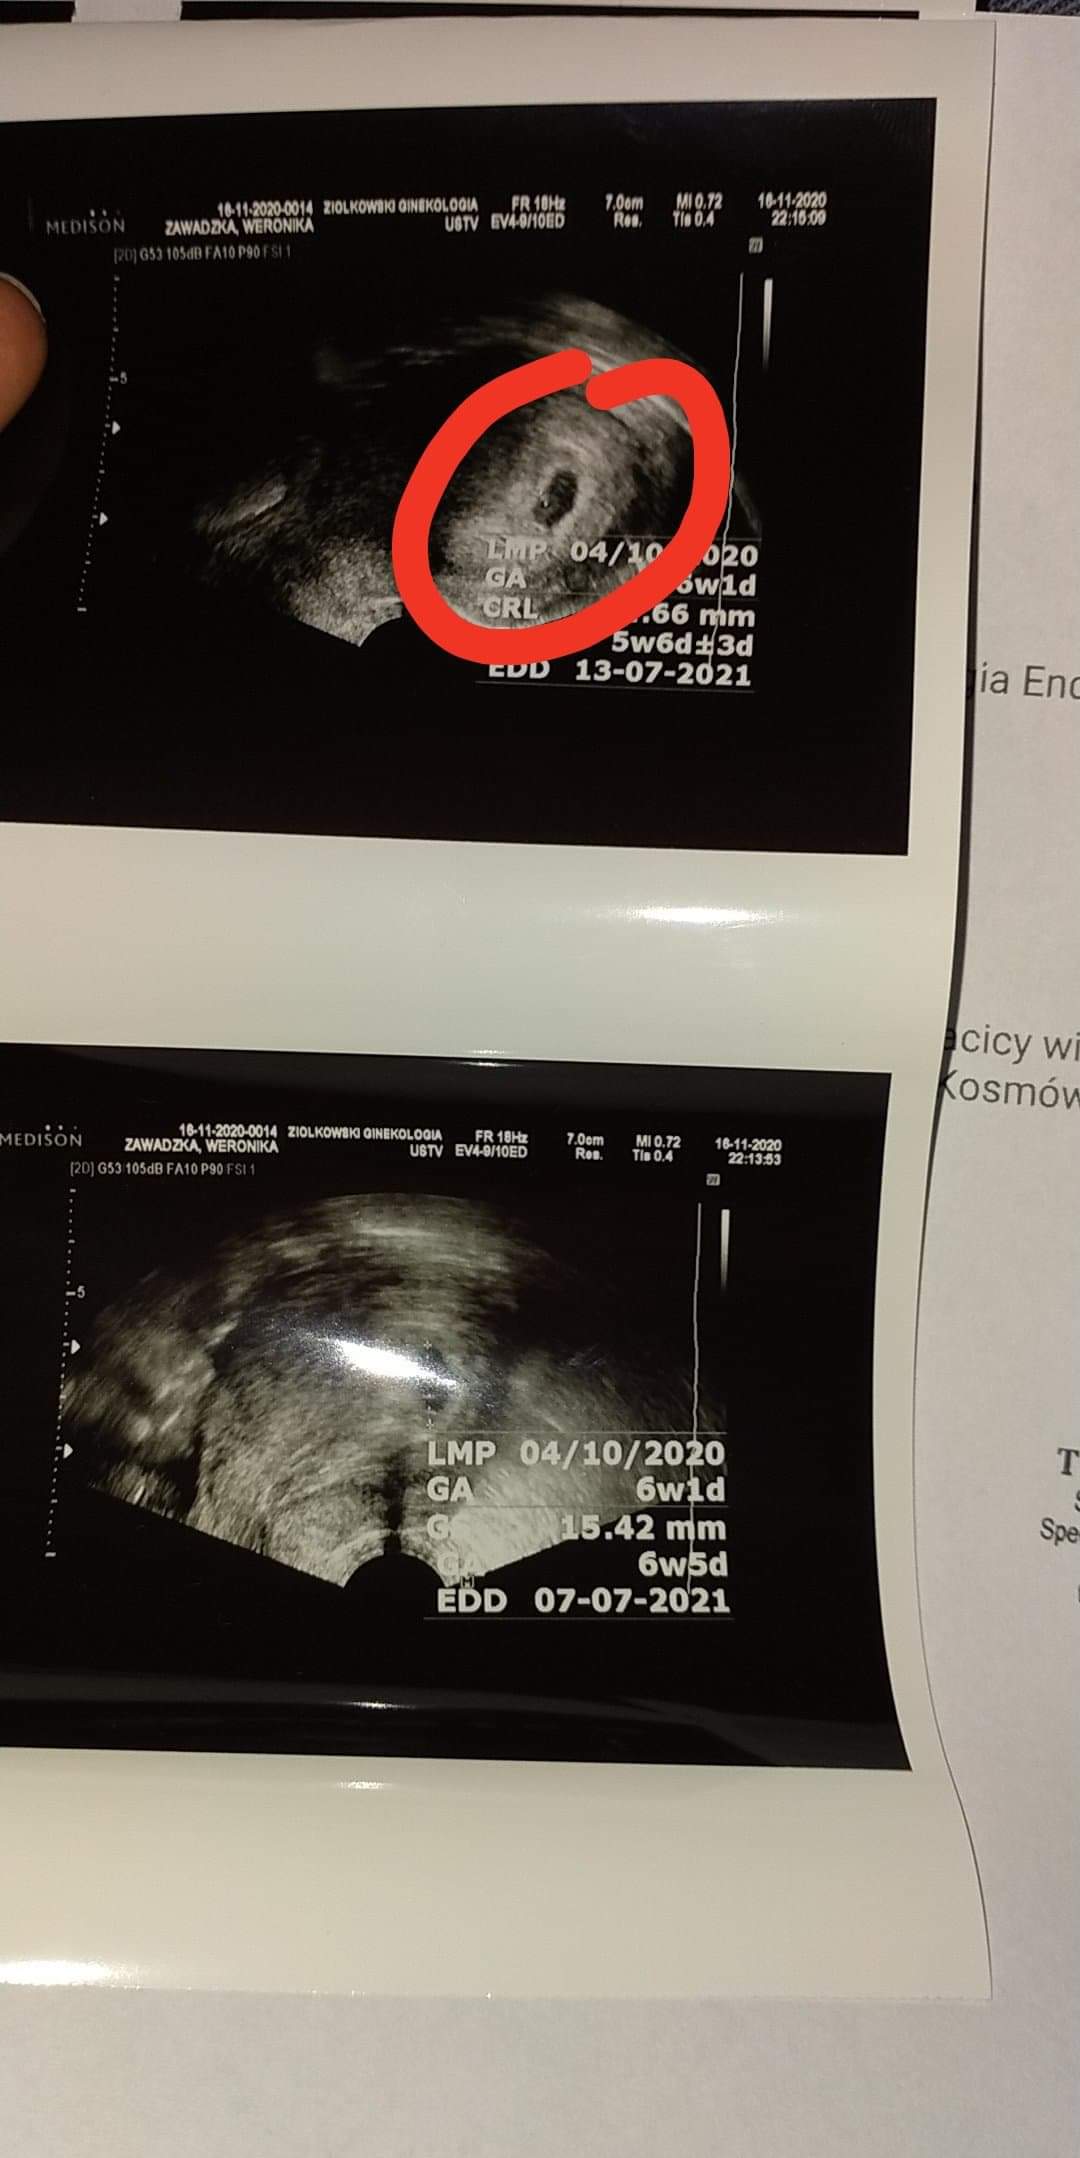

Witamy :) mamy się dobrze 😍❤️ obecnie 6 tydzień termin 10 lipca 😁😊

• received_656715021659677.jpeg

105,8 KB · Wyświetleń: 117